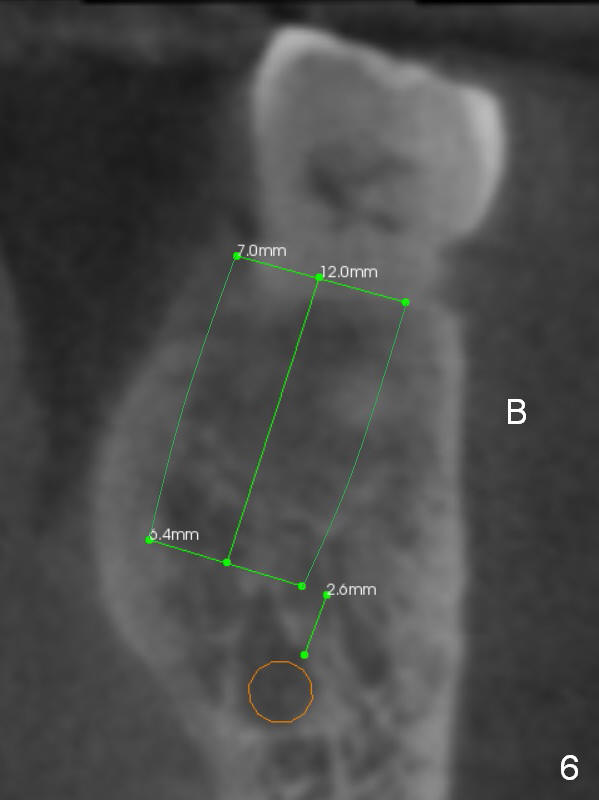

The shorter implant (10 mm (Fig.7 (coronal section)). as compared to 12 mm (Fig.6) more or less placed in the middle of the septum may decrease the chance to penetrate the coronal extension (Fig.8 brown triangle) of the Inferior Alveolar Canal (brown circle).